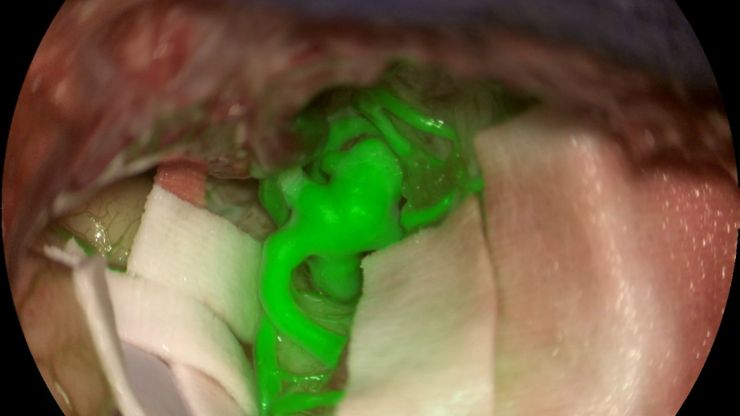

GLOW800增强现实荧光技术在动脉瘤治疗中的应用

Feres Chaddad博士教授的这个案例研究讨论了通过显微外科夹闭术治疗未破裂的MCA(大脑中动脉)和PCOM(后交通动脉)动脉瘤。这说明了增强现实荧光GLOW800借助实时血管血流增强技术,对大脑解剖结构获取增强实时视图,在动脉瘤夹闭前后为外科医生提供帮助。

Aneurysm shown with GLOW800 AR fluorescence application. Image courtesy of Prof. Jacques Guyotat, Hôpital Neurologique Pierre Wertheimer, Lyon